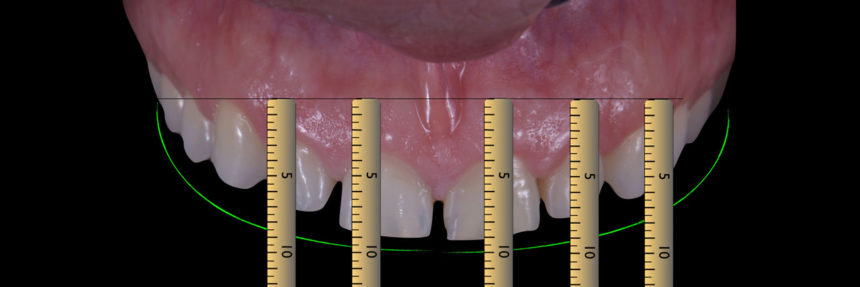

Demonstration of the mock up analyzing the esthetic aspects (LIVE)

Minimal invasive preparations for the veneers (LIVE)

categorization of veneers, teeth preparation techniques, silicon indexes, provisionals - mock-up, isolation techniques, cementation procedures

veneers try-in, isolation, cementation, finishing-polishing (LIVE)